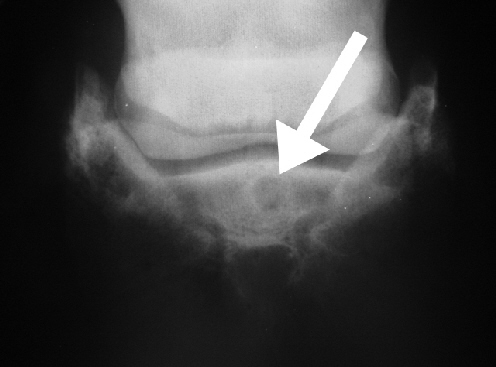

Röntgenbilder desselben Pferdes mit dem großflächigen Knorpeldefekt. Auf dem Röntgenbild sind zwar deutliche Arthroseerscheinungen sichtbar, lassen aber keinen sicheren Rückschluss auf das wirkliche Ausmaß des Knorpelschadens zu. Der rote Pfeil zeigt auf die Zubildungen am Kapselansatz (Schale). Die AP Aufnahme gibt einen Hinweis auf den rechts schmäleren Gelenkspalt.